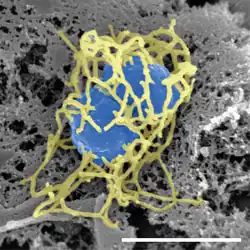

| Scanning electron micrograph of a single N. meningitidis cell (colorized in blue) with its adhesive pili (colorized in yellow). The scale bar corresponds to 1 µm. | |

N. meningitidis is spread through saliva and respiratory secretions during coughing, sneezing, kissing, chewing on toys and through sharing a source of fresh water. It has also been reported to be transmitted through oral sex and cause urethritis in men.[3] It infects its host cells by sticking to them with long thin extensions called pili and the surface-exposed proteins Opa and Opc and has several virulence factors.

Lipooligosaccharide (LOS) is a component of the outer membrane of N. meningitidis. This acts as an endotoxin and is responsible for septic shock and hemorrhage due to the destruction of red blood cells.[13] Other virulence factors include a polysaccharide capsule which prevents host phagocytosis and aids in evasion of the host immune response. Adhesion is another key virulence strategy to successfully invade host cell. There are several known proteins that are involved in adhesion and invasion, or mediate interactions with specific host cell receptors. These include the Type IV pilin adhesin which mediates attachment of the bacterium to the epithelial cells of the nasopharynx,[14][15] surface-exposed Opa and Opc proteins which mediate interactions with specific host cell receptors,[16] and NadA which is involved in adhesion.[17]